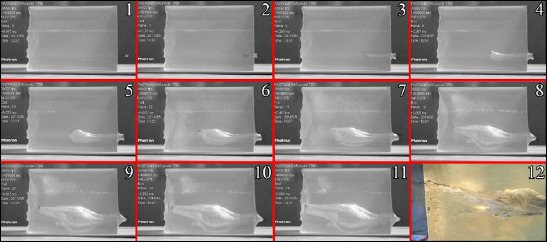

Methods: The study involved six Adana-breed sheep, aged 3-4 years, previously used in another study and showing no vital signs. Ethical approval was obtained from the local ethics committee. Test shots were conducted using 9×19 mm (M822), 5.56×45 mm (SS109), and 7.62×51 mm (M80) bullets from a distance of 300 cm, targeting the front legs of sheep positioned laterally. Following the shots, entry and exit wounds were photographed, and anteroposterior and lateral X-ray images of the extremities were taken for analysis. The aim was to examine the effects of different types of ammunition on extremities and provide insights into the characteristics of gunshot wounds.

Results: In the first test group (subjects A and B), X-ray imaging revealed joint integrity loss, multi-part fractures, and cavitation in the soft tissue, with bone fragments distributed along the exit trajectory. No bullet fragments were found within the wound cavity. The M822 bullet produced a typical entry wound and a smaller, more defined exit wound. In the second group (subjects C and D), SS109 bullets caused fragmentation of bone, muscle, tendon, and skin. Bullet fragments created a shrapnel-like effect. The exit wounds were larger and had irregular edges. In the third group (subjects E and F), M80 bullets caused extensive tissue disruption due to their high kinetic energy. The resulting exit wounds were wide and irregular.